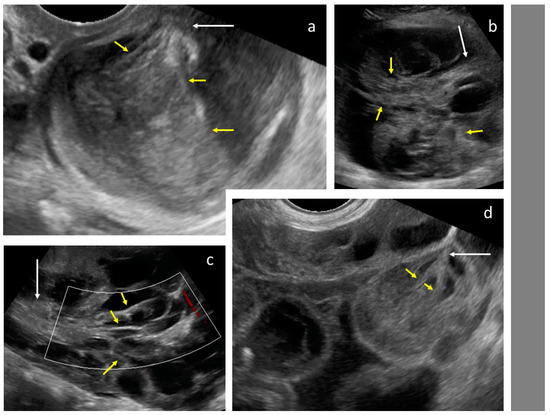

Figure 4.

Solid papillary projections (arrows) growing from the septa and inner wall. White dotted lines are measurements of the tumor.

After the collection of cases for the study was closed, a new observation was noted (by M.S.) when analyzing the videoclips of ovarian mCRC in detail. A tree-like sign was detected in multilocular-solid tumors, with parallel, closely-localized, septa (“trunk”) later branching in different directions (“branches”), forming an image resembling a tree (Figure 5, Video S3). Interestingly, the tree-like sign was not detected in any of matched controls with primary OC.

Figure 5.

Tree-like sign in a multilocular-solid tumor. White arrows indicate the “tree trunk”; yellow arrows indicate “tree branches”.